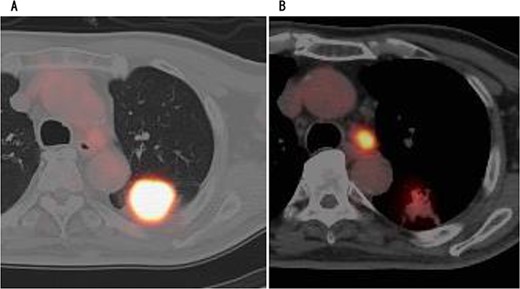

A 75-year-old male was referred to our hospital for preoperative examination of an abnormal chest shadow during orthopaedic surgery. Chest computed tomography (CT) revealed a mass nodule measuring 4.1 cm in S6 of the left lung, and the tracheobronchial lymph node (No 4 L) was enlarged (Fig. 1). Fluorodeoxyglucose positron emission tomography (PET) revealed abnormal accumulation with a maximum standardized uptake value of 20.4 at the mass, 9.4 at the lymph node and no metastases to other organs (Fig. 2). Based on the above findings, we diagnosed the patient with left lower lobe lung cancer (cT1bN2M0, c-Stage IIIA). The patient had no history of cardiovascular disease and was unaware of chest pain, such as an angina attack. We performed robot-assisted left lower lobectomy.

CT showed a circular mass measuring 4.1 cm in the S6 of the left lower lobe (A) and enlarged lymph node #4 (B).

PET showed high accumulation in the mass (A) and lymph node (B).